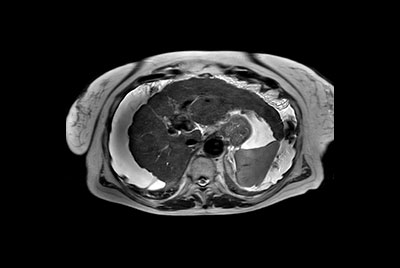

SmartSpeed Liver